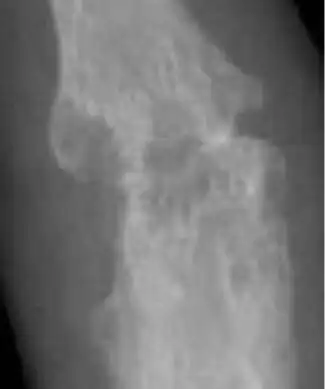

Bone erosion is a central feature of rheumatoid arthritis. Bone continuously undergoes remodeling by actions of bone resorbing osteoclasts and bone forming osteoblasts. One of the main triggers of bone erosion in the joints in rheumatoid arthritis is inflammation of the synovium, caused in part by the production of pro-inflammatory cytokines and receptor activator of nuclear factor kappa B ligand (RANKL), a cell surface protein present in Th17 cells and osteoblasts.[35] Osteoclast activity can be directly induced by osteoblasts through the RANK/RANKL mechanism.[36]

![Bone erosions by rheumatoid arthritis.[38]](./_assets_/0c70a452f799bfe840676ee341124611/X-ray_of_right_fourth_PIP_joint_with_bone_erosions_by_rheumatoid_arthritis.jpg)